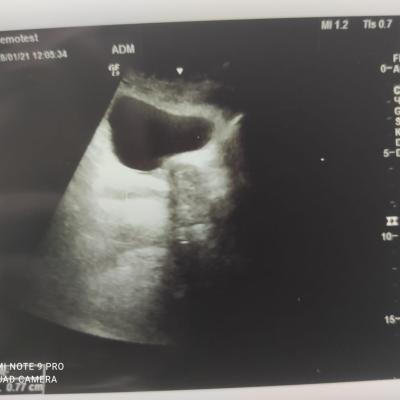

Здравствуйте! При наличии коралловидного камня правой почки(заключение УЗИ), можно предположить причиной боли нарушение уродинамики верхних мочевых путей), что, однако, не подтверждается результатами УЗИ почек( ЧЛС не расширена). Другая, наиболее вероятная возможная причина "боли в боку" - может быть патология опорнодвигательного аппарата. Необходимо проконсультироваться с неврологом и урологом очно, и согласовать возможность применения противовоспалительных, обезболивающих и спазмолитических препаратов - как первый шаг. В дальнейшем необходимо планировать возможное дальнейшее обследование и лечение. Удачи!